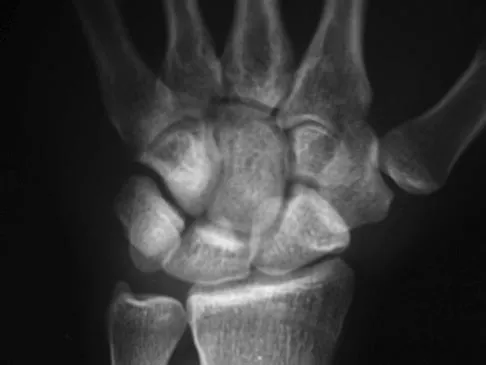

A 45-year-old man is seeking evaluation of an injury sustained in a motor vehicle accident 10 weeks ago. Current radiographs are shown in Figures 2a and 2b. Based on the radiographic findings, what is the most likely diagnosis?

Explanation

An increased density of the talar body compared to the distal tibia following fracture of the talar neck is highly suggestive of vascular compromise of the talar body. Subchondral osteopenia of the talus at 6 to 8 weeks (Hawkins sign) is a favorable sign but does not eliminate the possibility of osteonecrosis. Elgafy H, Ebraheim NA, Tile M, Stephen D, Kase J: Fractures of the talus: Experience of two level 1 trauma centers. Foot Ankle Int 2000;21:1023-1029.